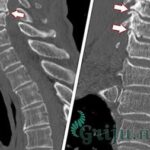

Причинами возникновения данного патологического явления могут стать разные грыжи, перепады температур, онкологические заболевания и прочие неблагоприятные моменты, перечислять которые можно очень и очень долго и утомительно. Для того, чтобы опровергнуть собственные страхи и предрассудки, стоит обязательно пройти процедуру простейшей рентгенографии, которая будет очень кстати при постановке окончательного диагноза. При особой надобности доктором может быть назначено прохождение магнитно-резонансной либо простой компьютерной томографии, которая покажет состояние скелета более детально.

Неплохой результат может показать ультразвуковое исследование поверхности суставов, которое покажет, в какой степени развития находится данный недуг. Делается это абсолютно без анестезии, так как болевых ощущений не вызывает никаких. Вполне эффективна в этом вопросе процедура МРТ-исследования, которая не причиняет никакого вреда здоровью обратившегося, но при этом показывает ошеломительную точность. К тому же, данный метод позволяет рассмотреть костную ткань в организме послойно, что дает возможность составить более подробную клиническую картину состояния пациента. Еще один, пожалуй, один из самых важных плюсов кроется в том, что увидеть при помощи данного метода можно любые, даже самые незначительные изменения в костях обратившегося.